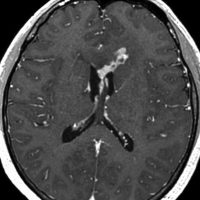

左はICE化学療法 (IFO/CDDP/VP-16)前,右は1コース終了後です。腫瘍は顕著に縮小してgerminomaとして普通の化学療法反応性を示します。また,松果体と下垂体には腫瘍はありません。